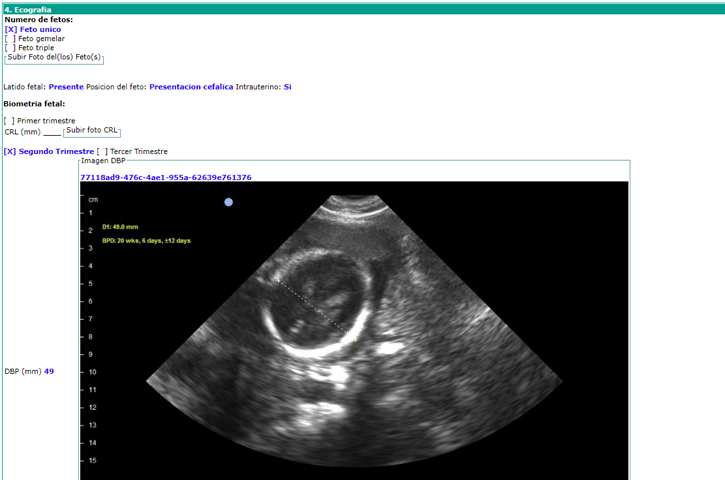

Uno de los Sistemas de Información de Salud (SIS) desplegados por EHAS ha sido el que sistematiza los datos de salud del proyecto “Embarazo Saludable” en Guatemala. La iniciativa acerca a las comunidades rurales pruebas determinantes para detectar riesgos en el embarazo, como la ecografía obstétrica y los análisis de sangre y orina. La información e imágenes de ecografía generadas en los controles prenatales son registradas por el personal de enfermería que cubre las áreas rurales en un sencillo SIS basado en la plataforma de Software Libre OpenMRS.

Esta herramienta puede utilizarse sin necesidad de conexión a Internet, almacenando los datos de manera local y sincronizándolos en la nube una vez que el personal de enfermería regresa una zona con conectividad, lo que resulta especialmente útil en entornos rurales. Una vez registrada, la información es accesible a especialistas en Ginecología para que puedan validar el diagnóstico a distancia de cada caso, resolver dudas para mejorar la realización de las pruebas, y facilitar, en definitiva, el seguimiento y la evaluación con los indicadores actualizados de salud materna y neonatal generados por el proyecto.